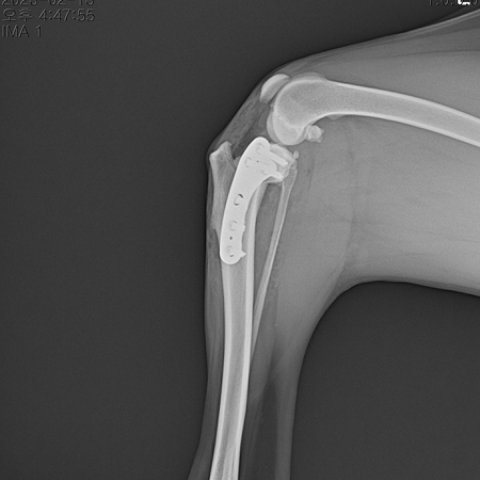

TPLO, CTWO, ECF µî ´Ù¾çÇÑ ¼ö¼ú ¹æ¹ýÀÌ ÀÖ¾î¿ä. ±× Áß TPLO°¡ °¡Àå ¿¹Èİ¡ ÁÁ¾Æ¿ä. ´Ù¸¥ ¼ö¼ú¹æ½Ä¿¡ ºñÇØ »¡¸® ȸº¹µÇ°í ºÎÀÛ¿ëµµ ´ú ÇÑ ÆíÀÌÁÒ. ÇÏÁö¸¸ ¸ðµç ¼ö¼úÀº ¼·Î ´Ù¸¥ Àå´ÜÁ¡À» °¡Áö°í ÀÖ°í °æ¿ì¿¡ µû¶ó TPLO°¡ ºÒ°¡´ÉÇÑ ¾ÆÀ̵éÀÌ ÀÖ¾î¿ä. ÀÌ·² °æ¿ì ´Ù¸¥ ¹æ½ÄÀÇ ¼ö¼úÀ» ÁøÇàÇØ¾ß µÅ¿ä.

TPLO

ECF